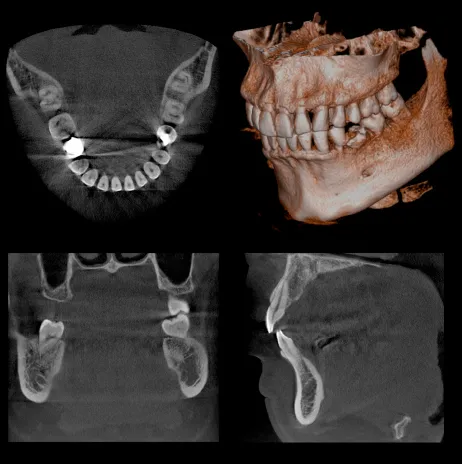

通常のX線撮影では、歯やアゴの骨の状態を二次元でしか確認できないため、色々な病状(歯の根の病気や歯周病の病状)を見落としてしまう可能性は否定でき ません。CTを撮影することによって、あらゆる方向から三次元で歯やアゴ骨の状態を確認可能なため、詳細な診断が可能になります。

撮影時間も9.4秒と極めて短く、放射線の被曝量は、医科用CT撮影(頭部)の1/77~1/23以下です。

限られた病変(歯の神経の治療、歯周病の治療、親知らずの抜歯など)においては保険適用での撮影が可能です。

また、インプラントの手術をする際には、アゴの骨の状態を診査するには必ずCT撮影が必要であり、その後の定期診査にも非常に有効です。

医科用CT撮影に比べると少ないながらも、被爆のデメリットもありますので、必要に応じて使用し、診査・診断に大いに役立てていきたいと思います。